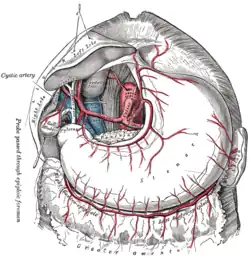

The cystic artery branches from the right hepatic artery. | |

The cystic artery lies within the hepatobiliary triangle. The triangle is used to locate the cystic artery during a laparoscopic cholecystectomy.

The triangle contains: adipose and connective tissue, lymphatic vessels and the cystic lymph node, autonomic nerves, (usually) cystic artery, and (sometimes) an accessory cystic duct.[3] The right hepatic artery may also pass through the hepatobiliary triangle.[2]

The anatomy and variant anatomy of this region is important during gallbladder removal to prevent iatrogenic injury to the common hepatic duct, bile duct, or right hepatic artery.[3]

The cystic artery lies within the hepatobiliary triangle, which is used to locate it during a laparoscopic cholecystectomy.[4][5] It may also contain an accessory right hepatic artery or an anomalous sectoral bile ducts. As a result, dissection in the triangle of Calot is ill-advised until the lateral-most structures have been cleared and identification of the cystic duct is definitive. According to SESAP 12 (produced and distributed by the American College of Surgeons) dissection in the triangle of Calot is the most common cause of common bile duct injuries.